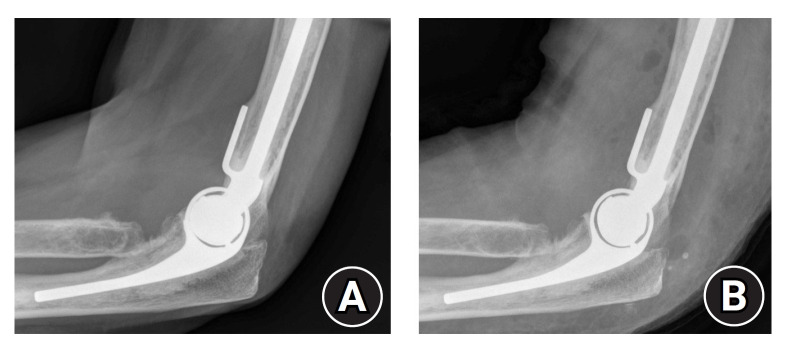

Abstract Image